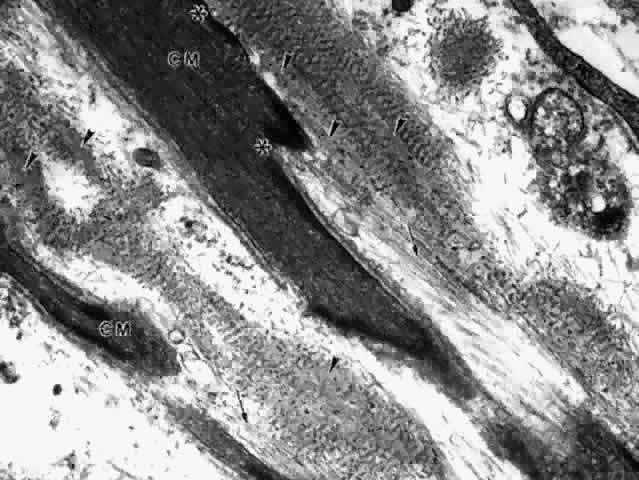

Fig. 30. Pars plicata of the ciliary body cut coronally, perpendicular to the usual plane. Ciliary muscle (CM) does not extend into the ciliary processes, but has the same thickness under processes and valleys. The anterior hyaloid membrane is visible above the processes (arrowheads). (hematoxylin-eosin, X 120)

The great bulk of the ciliary muscle lies in the anterior two thirds of the ciliary body (see Fig. 5). At the light microscopic level in the child, the longitudinal muscle shows a primary attachment to the scleral spur and to the outer corneoscleral and uveal trabecular meshwork, while the oblique radial fibers have more connection to the inner uveal meshwork (see Fig. 34). The circular muscle attachments are primarily to the adjacent ciliary and iris root stroma. During aging the addition of significant fibrous tissue and hyaline greatly increases the bulk of the radial and circular muscles (Fig. 36) but not the longitudinal muscle. Tamm, Tamm, and Rohen44 found that connective tissue comprised about half of the oblique muscle in the 50- to 60-year-old age group. The circular muscle was also significantly increased in area and partially separated from the oblique muscle by this connective tissue, which was continuous with hyaline in the processes. The overall effect of aging on the ciliary muscle made it shorter in length and greater in area with a prominence of the circular muscle, resulting in a forward and inward configuration resembling the accommodated state. Others have described some atrophy of the muscle with decreased nuclei, particularly in the circular muscle and over the age of 40 years.45

Fig. 36. Dense pale hyaline deposition (arrow) between the circular (C) and radial (R) but not the longitudinal (L) muscle bundles of a 64-year-old patient. Compare with Figure 34 from 2-year-old child. (hematoxylin-eosin, X 250)